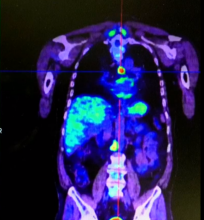

A 61-year-old man was admitted due to a left main bronchus mass accidentally discovered during cardiac investigations conducted for sporadic episodes of syncope, fatigue, and cough, which increased during a period of one month. Computed tomography (CT) and positron emission tomography (PET) revealed a 13 mm mass arising from the left main bronchus near the carina. The lung parenchyma appeared normal and no mediastinal or hilar lymph node involvement was detected. A flexible bronchoscopy was performed and a sessile endobronchial mass with hyperemic appearance was found. The lesion originated from the membranous portion of the left main bronchus, immediately close to the carinal bifurcation and it occupied more than 80% of the bronchus lumen. A biopsy was conducted on the specimen, which resulted in the diagnosis of a GT. The patient was thus a candidate for surgery, and a left main bronchus sleeve resection with end-to-end anastomosis via a transsternal transpericardial approach was performed, as shown in the video. The patient’s postoperative course was uneventful and they were discharged nine days after surgery. Before hospital discharge, a flexible bronchoscopy showed no stenosis or leakage of the anastomosis. At a three-month follow-up visit, the patient was in good physical condition and no recurrences were detected.